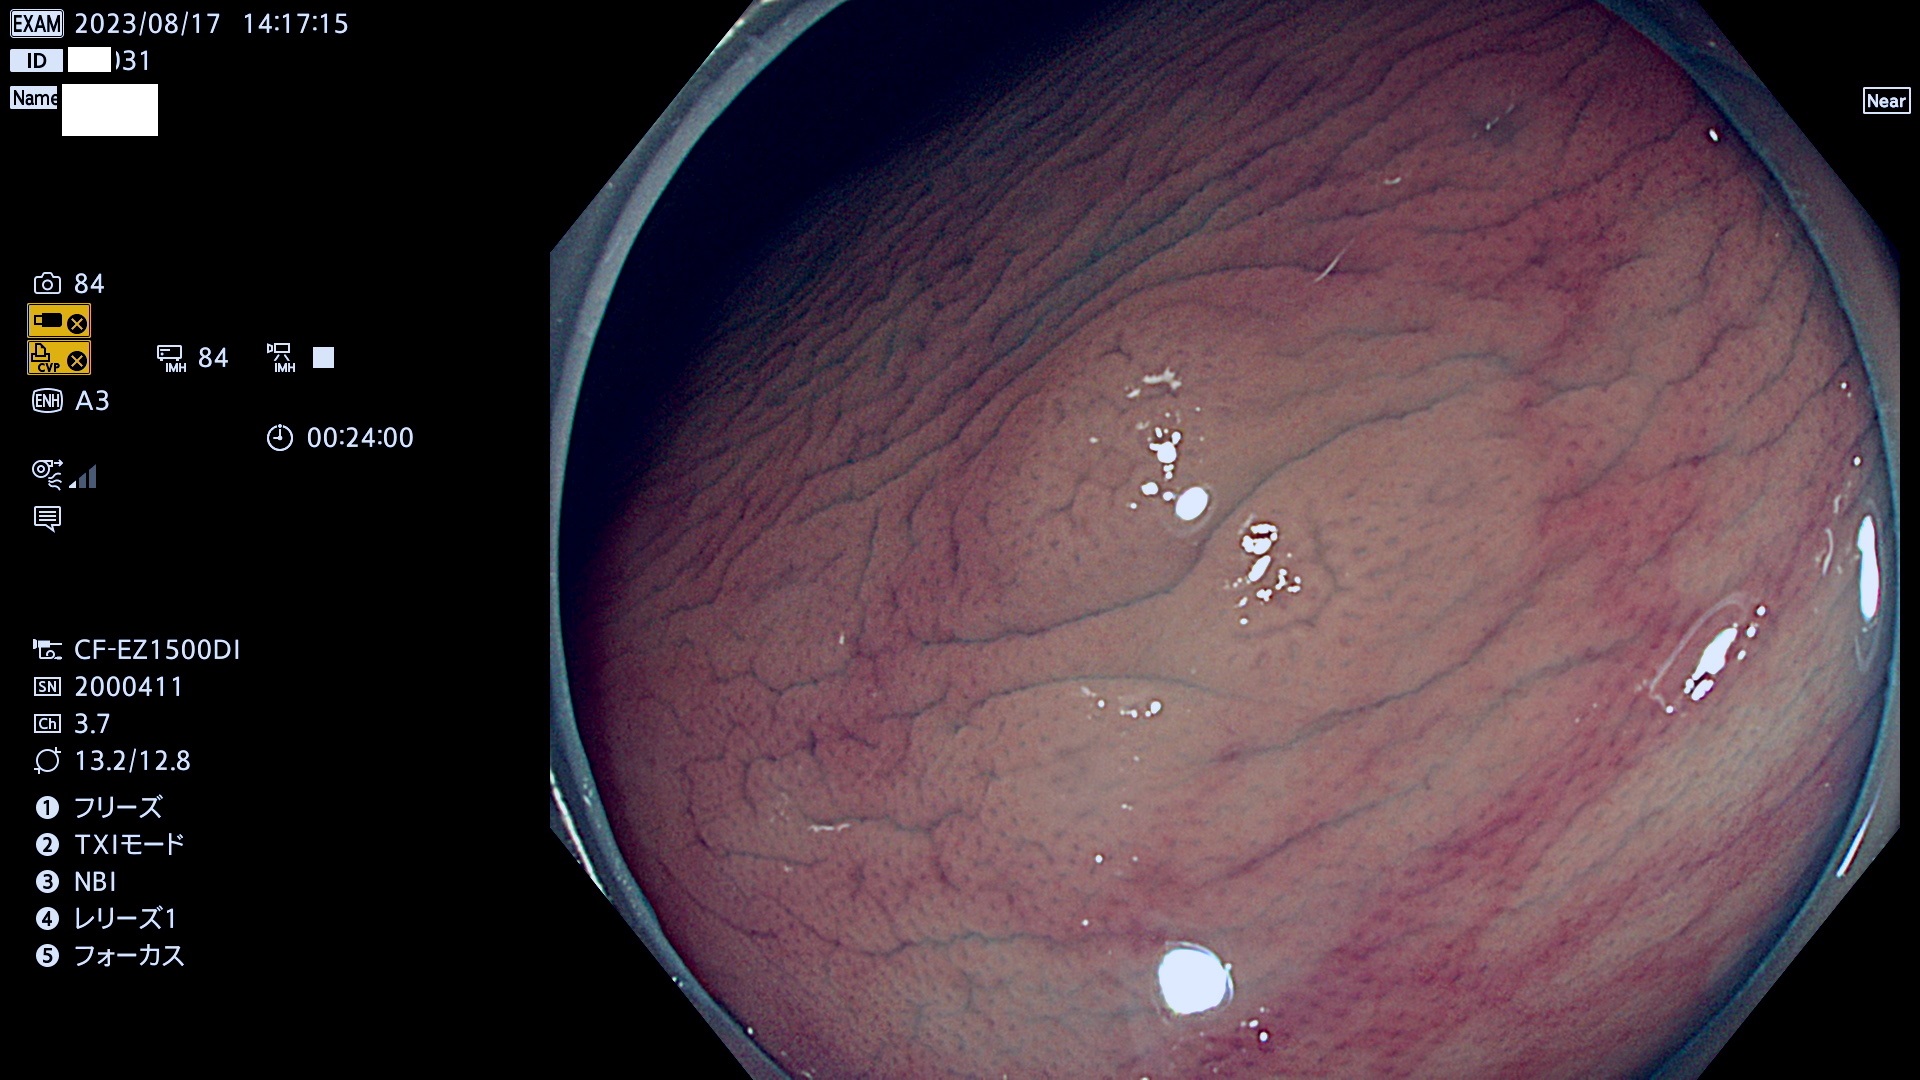

表面型腺腫(Flat Adenoma)の中で、完全に平坦な物をUb、陥凹している物をUcと呼びます。平坦隆起型(Ua)よりも、発見が難しく危険な病変です。このタイプは「内視鏡後・大腸癌の重要犯人」であり、この発見率は「腺腫発見率」よりも、重要な意味があります。

毎週の検査(木・金・土・日)に発見されたUb、Uc型・腺腫を、その週の日曜の夜にUPし1週間、提示します。

抽出の対象期間 2023年8月17日(木)〜8月20(日)の4日間(48件の検査)11件